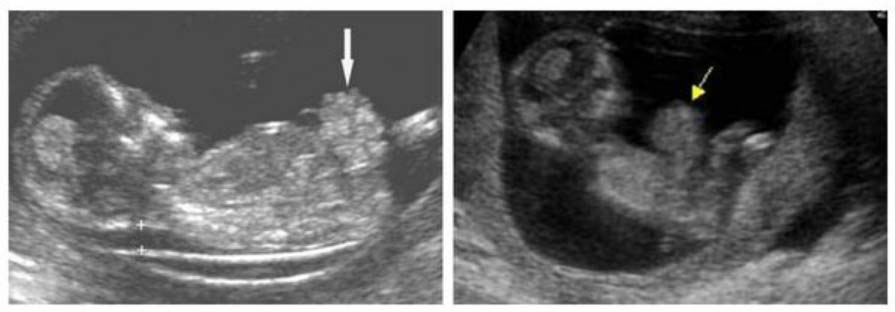

В настоящее время в диагностике гастрошизиса ключевую роль играют методы пренатальной диагностики, в частности ультразвуковое исследование плода. Это позволяет выявить патологию уже на 10-13 неделе беременности. Окончательный диагноз гастрошизиса устанавливается на 13-14 неделях, что связано с возможностью самостоятельного вправления выпавшего кишечника и полного заживления дефекта к 12 неделе гестации. При проведении УЗИ можно обнаружить анэхогенные тонкостенные округлые структуры трубчатой формы, находящиеся за пределами брюшной полости и не имеющие оболочек. К сопутствующим признакам относятся маловодие/ многоводие, а также признаки внутриутробной задержки развития плода.